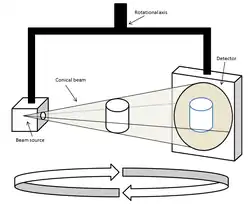

Cone beam computed tomography (or CBCT, also referred to as C-arm CT, cone beam volume CT, flat panel CT or Digital Volume Tomography (DVT)) is a medical imaging technique consisting of X-ray computed tomography where the X-rays are divergent, forming a cone.[1]

During dental/orthodontic imaging, the CBCT scanner rotates around the patient's head, obtaining up to nearly 600 distinct images. For interventional radiology, the patient is positioned offset to the table so that the region of interest is centered in the field of view for the cone beam. A single 200 degree rotation over the region of interest acquires a volumetric data set. The scanning software collects the data and reconstructs it, producing what is termed a digital volume composed of three-dimensional voxels of anatomical data that can then be manipulated and visualized with specialized software.[2][3] CBCT shares many similarities with traditional (fan beam) CT however there are important differences, particularly for reconstruction. CBCT has been described as the gold standard for imaging the oral and maxillofacial area.